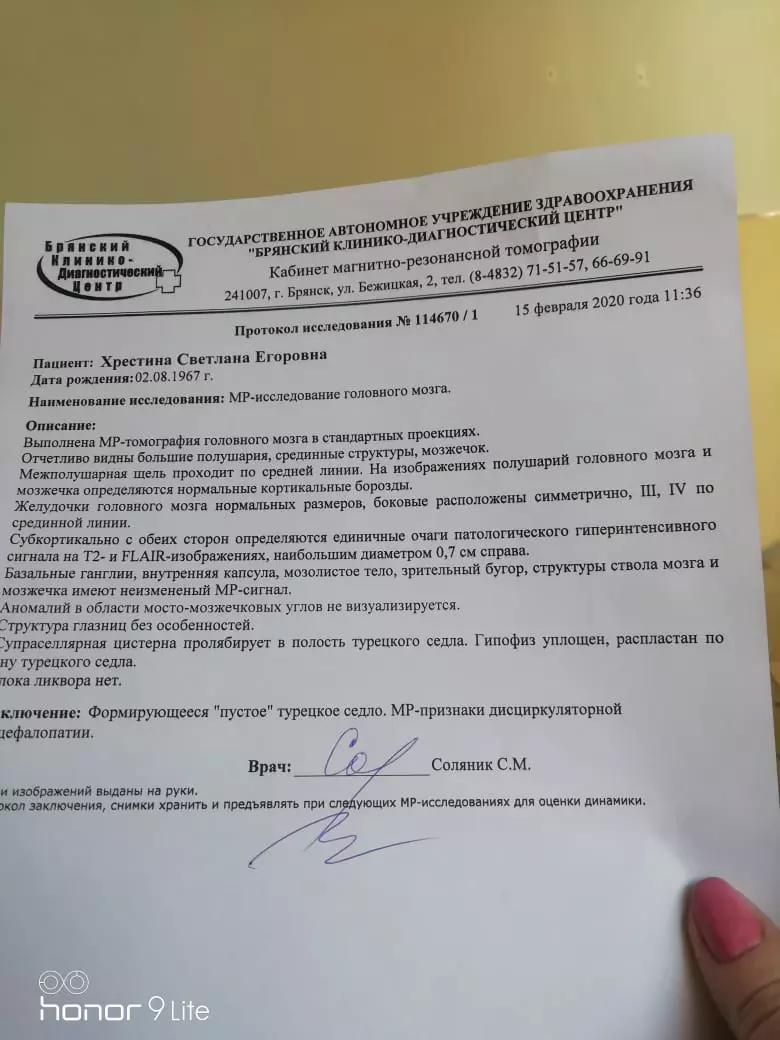

МРТ головного мозга: Расшифровка снимков и Интерпретация

Раздел: Визуальные уроки